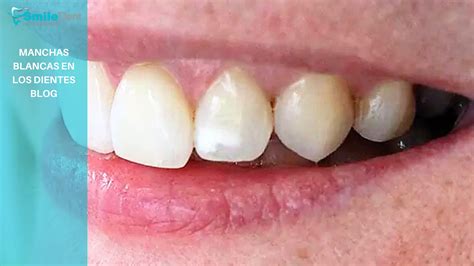

Manchas Blancas en los Dientes

En algunos niños también aparecen manchas blancas en los dientes mientras éstos se desarrollan. Las manchas blancas pueden aparecer con frecuencia en bebés que beben de biberón, pudiendo aparecer las llamadas caries de biberón.

Las manchas blancas en los dientes pueden ser el resultado de varias cosas. Pueden ser el resultado de la hipoplasia del esmalte (capa externa del diente), que es una falta de minerales. La hipoplasia del esmalte se debe a que durante la formación de los dientes no ha habido una mineralización correcta del esmalte dental y aparecen manchas blancas, sobre todo visibles en los dientes superiores de delante (incisivos). Se trata un defecto del esmalte dental que hace que los dientes tengan menos cantidad de esmalte de lo normal.

Las manchas blancas en los dientes pueden aparecer después de que se hayan producido cambios en el contenido mineral de los dientes de una persona (que sucede a menudo durante la infancia). También pueden aparecer en relación con una condición llamada fluorosis, que es el resultado de tener una ingesta excesiva de flúor durante el período de formación de los dientes.

Las lesiones de mancha blanca también son comúnmente atribuidas a tener brackets u ortodoncia. Las personas con aparatos de ortodoncia a menudo tienen problemas para cepillarse correctamente los dientes y el resultado es una acumulación de placa (bacterias orales). Los ácidos, producto de estas bacterias, pueden dañar gravemente esmalte (capa externa) de los dientes y causar caries.

Antes una mancha blanca la primera visión diagnóstica es diferenciarlo de un estadio inicial de caries o no. Se debe, ante todo, realizar una prevención de la caries. Esta puede realizarse mediante un control de la placa, ya sea con un cepillado dental, como un control químico de este.

Tratamientos para las Manchas Blancas

Los tratamientos para la hipoplasia dental o para las manchas blancas de los dientes suelen variar según la gravedad y severidad de la mancha. Normalmente, se suele usar una técnica llamada microabrasión dental para los casos más leves. En el caso de manchas más severas, es necesario optar por otro tipo de tratamiento como la colocación de carillas de porcelana.